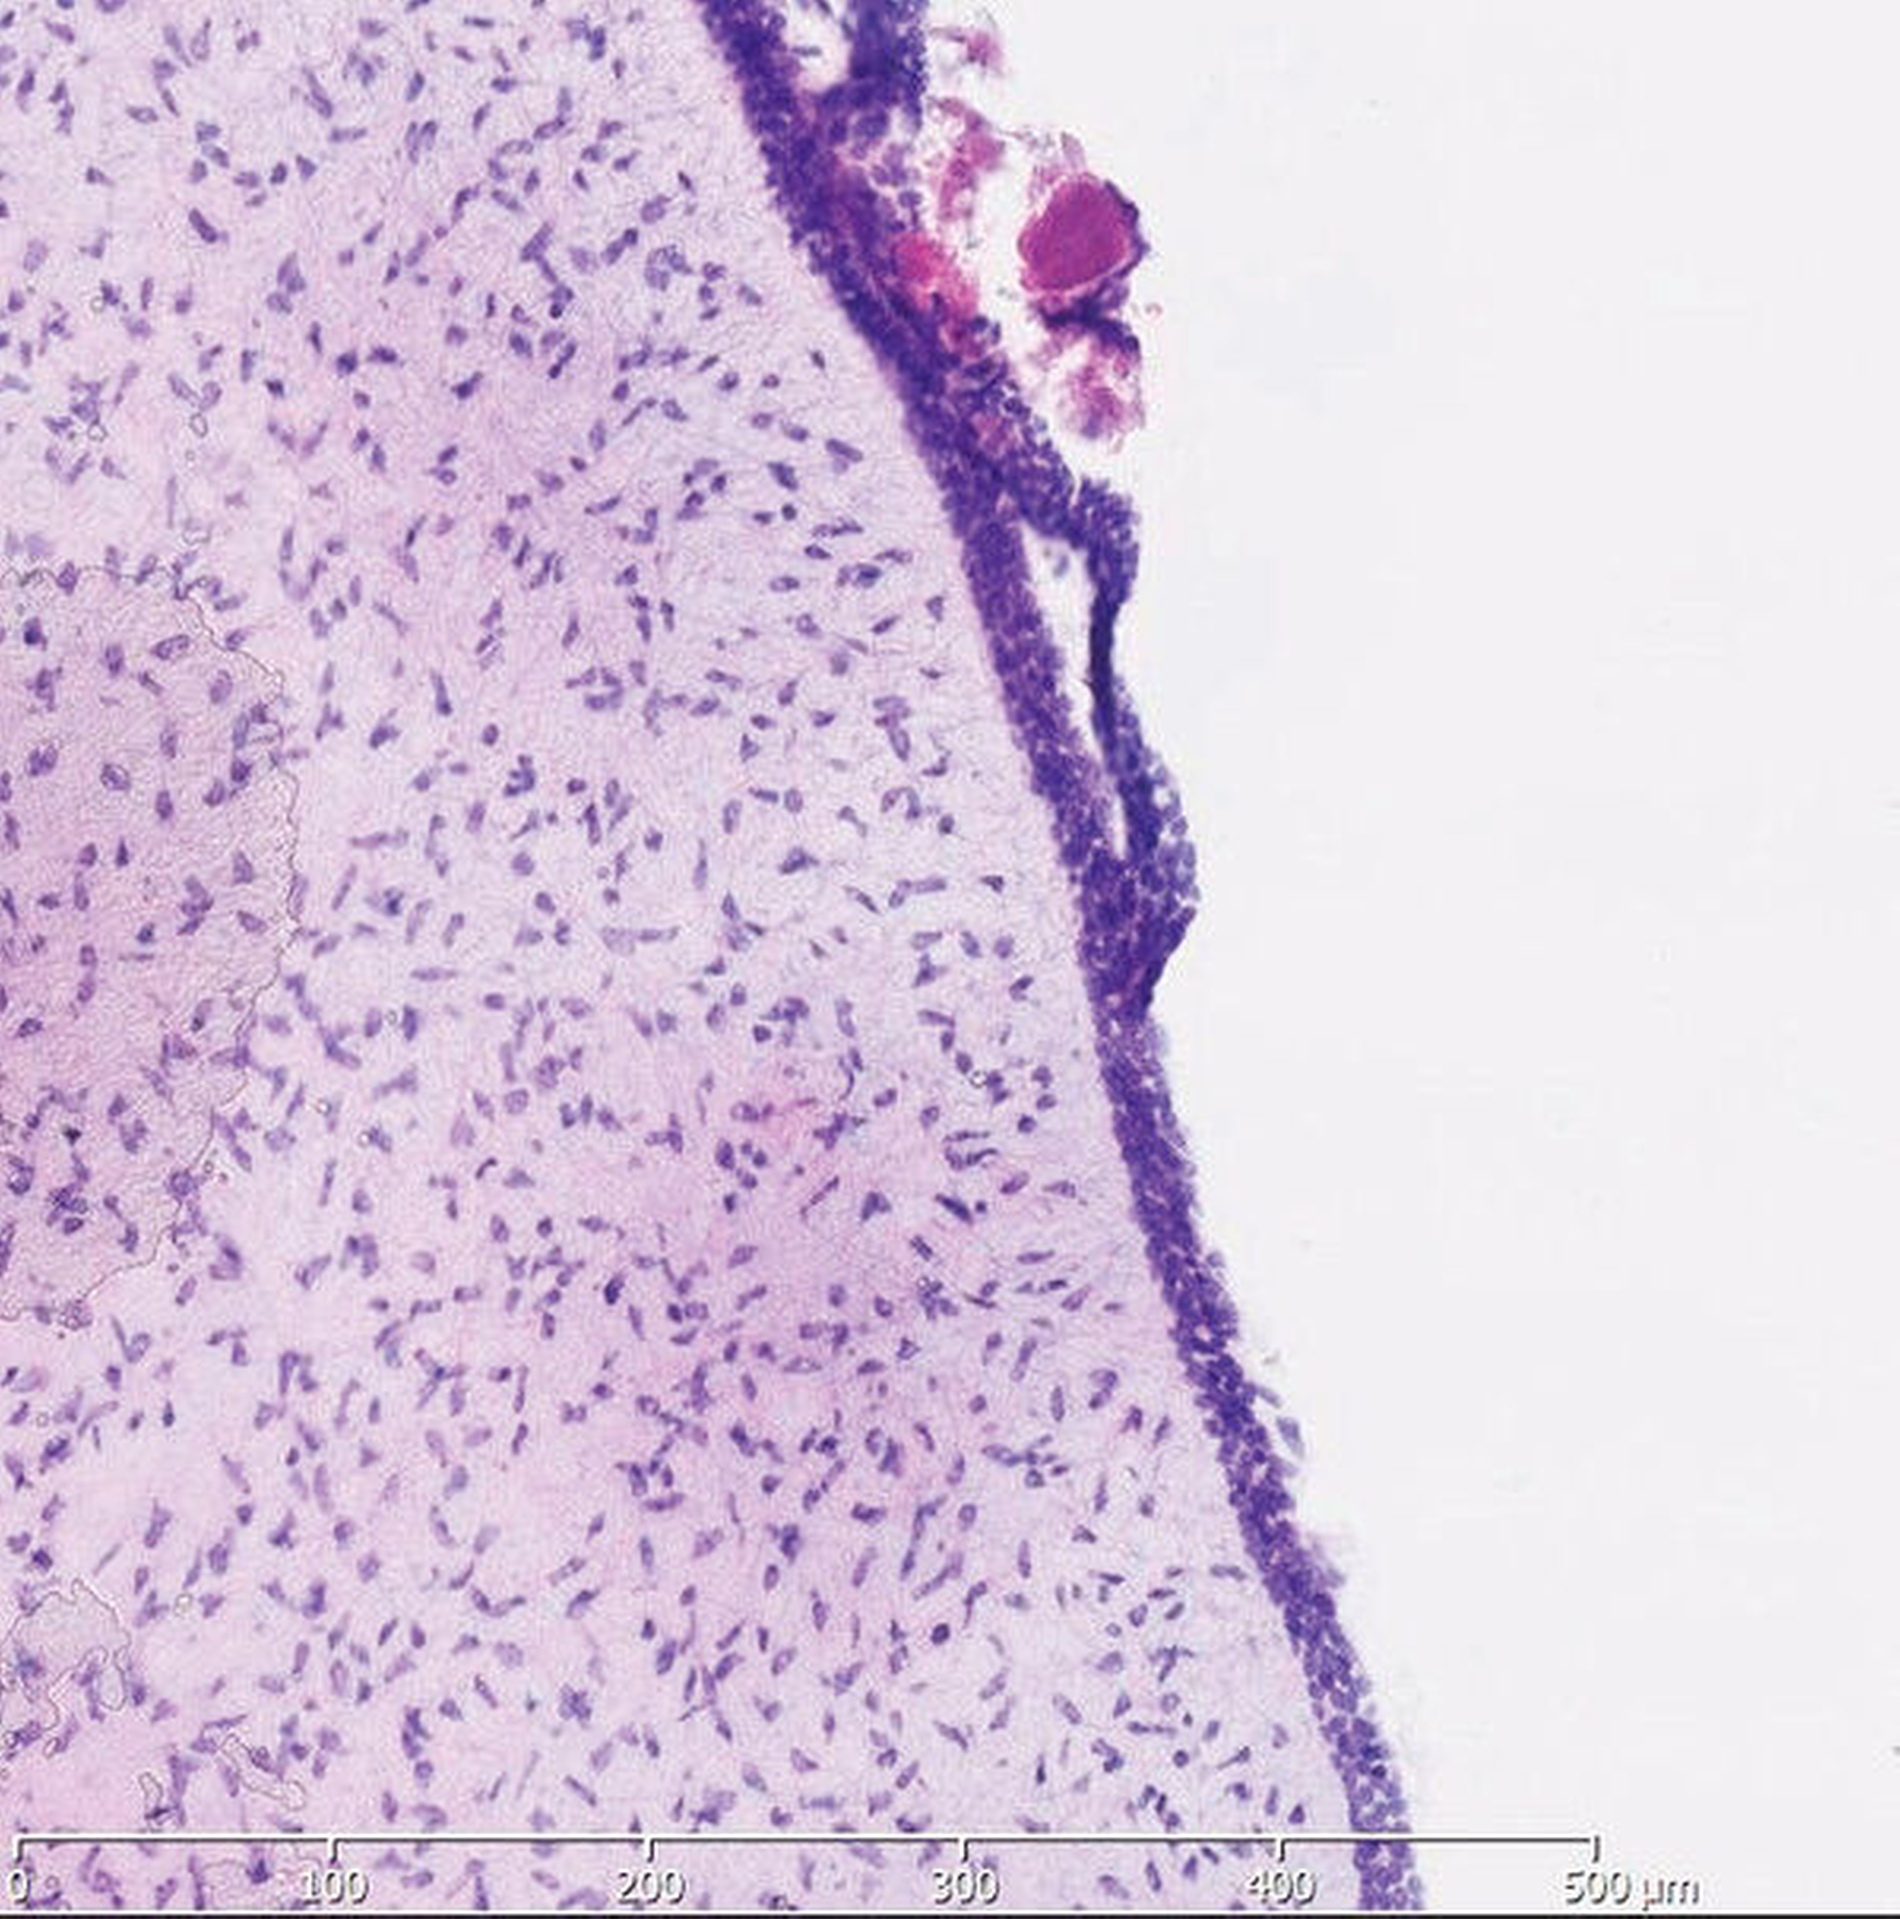

In der histopathologischen Aufarbeitung fand sich spindelzelliges Gewebe mit myxoidem Aspekt, teils eher zellreich mit allenfalls geringgradigen Kernatypien (Abbildungen 7 und 8).

Die Läsion schloss mehrfach kleine Nervenstrukturen ein und kleine kapilläre Gefäße. Randlich und intraläsional zeigten sich neugebildetes beziehungsweise remodelliertes Geflechtknochengewebe mit vermehrten Osteoblasten. In der Pulpa der unreifen Anlage des Zahns 13 imponierten fibromyxoide Gewebekomponenten. Unter Berücksichtigung des vollständig aufgearbeiteten histopathologischen Gesamtbefunds ist von einem odontogenen Myxom mit Assoziation zu einer Zahnanlage auszugehen.